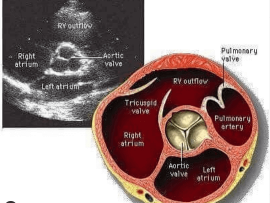

Lee masBeautiful illustrative picture about the parasternal short axis view, great vessel level Mohammed Zidan, MBBCH, M.Sc Cardiology (Cardiology, Echocardiography and interventional Cardilogy Specialist at Al-Azhar university), Cairo, Egypt...